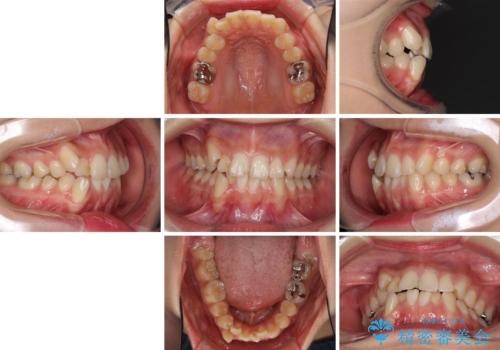

- 上下の八重歯を気にして来院された患者様です。

上下ともに八重歯の後ろの歯を1歯ずつ抜歯し、補助装置(リンガルアーチ)を用いて八重歯の位置を改善し、その後インビザラインにより矯正治療を行うこととしました。

途中海外留学をされたため、治療期間は長くなりましたが、事前に補助装置やワイヤー装置を併用したことで、きれいな歯列に仕上げることができました。